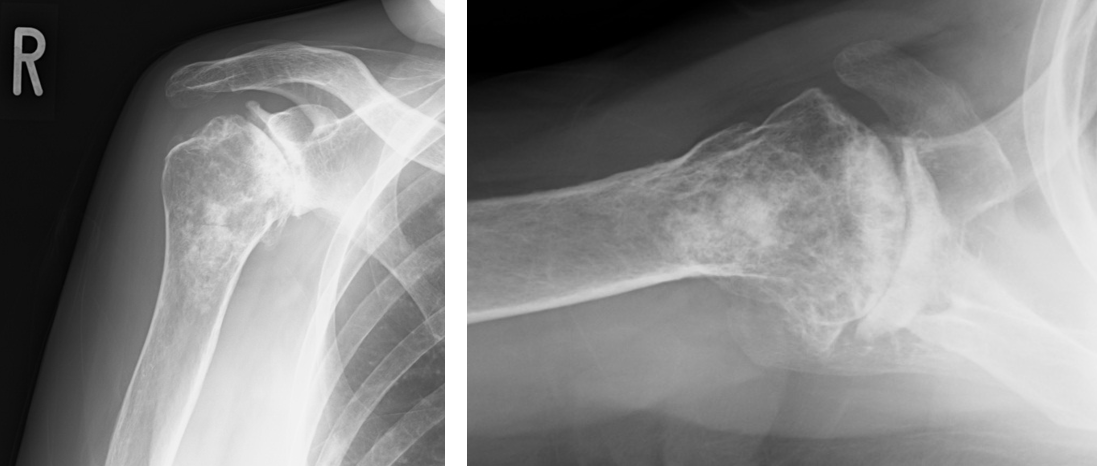

手術前のレントゲンです

手術前のレントゲン